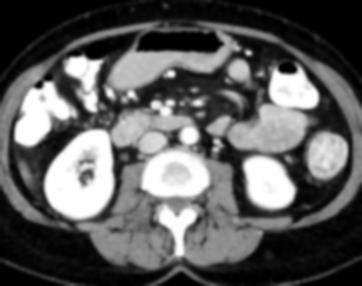

Due to the constraints of the imaging device and high cost in operation time, computer tomography (CT) scans are usually acquired with low intra-slice resolution. Improving the intra-slice resolution is beneficial to the disease diagnosis for both human experts and computer-aided systems. To this end, this paper builds a novel medical slice synthesis to increase the between-slice resolution. Considering that the ground-truth intermediate medical slices are always absent in clinical practice, we introduce the incremental cross-view mutual distillation strategy to accomplish this task in the self-supervised learning manner. Specifically, we model this problem from three different views: slice-wise interpolation from axial view and pixel-wise interpolation from coronal and sagittal views. Under this circumstance, the models learned from different views can distill valuable knowledge to guide the learning processes of each other. We can repeat this process to make the models synthesize intermediate slice data with increasing inter-slice resolution. To demonstrate the effectiveness of the proposed approach, we conduct comprehensive experiments on a large-scale CT dataset. Quantitative and qualitative comparison results show that our method outperforms state-of-the-art algorithms by clear margins.